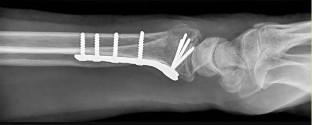

- الكسور: تُعد كسور عظام اليد والمعصم من الأسباب الشائعة للألم والخلل الوظيفي. تتضمن كسور السلاميات، العظام المشطية، عظام الرسغ (مثل كسر العظم الزورقي)، وكسور الكعبرة البعيدة (Distal Radius Fractures). قد تحدث هذه الكسور نتيجة السقوط على يد ممدودة، الإصابات الرياضية، أو حوادث السيارات.

- الأشعة السينية (X-rays): هي الخطوة الأولى في تقييم الكسور، الخلوع، وتغيرات التهاب المفاصل. تساعد في تحديد مدى تدهور العظام والمسافات المفصلية. على سبيل المثال، تُظهر صور الأشعة السينية كسور السلاميات

. - الأشعة المقطعية (CT Scan): توفر صوراً تفصيلية ثلاثية الأبعاد للعظام، وهي مفيدة جداً لتقييم الكسور المعقدة، مثل كسور العظم الخطافي (Hamate Hook Fracture) التي قد لا تظهر في الأشعة السينية العادية